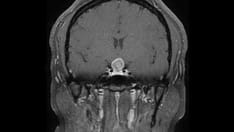

Histopathologic slide demonstrating a glioblastoma multiforme.